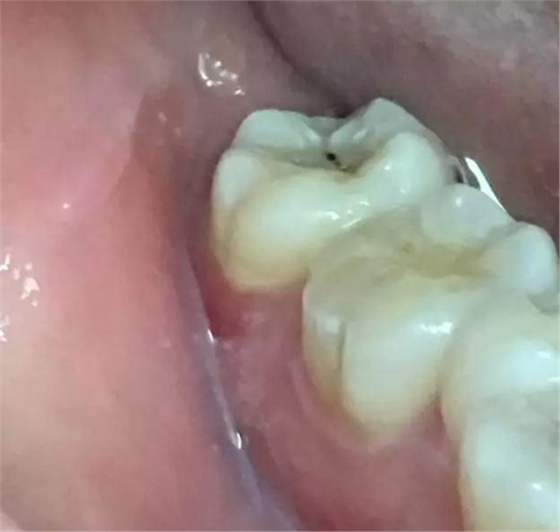

圖1.患者自述右側(cè)下后牙牙齦紅腫,咀嚼不適。術(shù)前口內(nèi)像:37頰側(cè)牙齦紅腫

圖2.術(shù)前的x線根尖片影像檢查:47遠中牙根吸收。